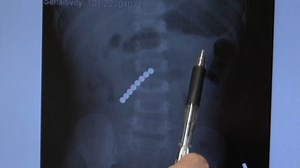

Consumer Product Safety Commission issues new magnet s

2022年9月7日

6abc Philadelphia